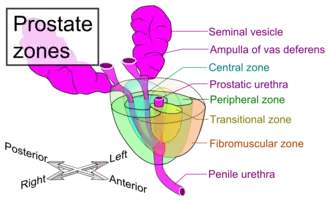

Anatomisch lässt sich die Prostata in einen rechten, linken und mittleren Lappen untergliedern: Lobus prostatae dexter, Lobus prostatae sinister und Isthmus prostatae (Lobus medius). Die funktionelle Gliederung in Zonen nach McNeal unterscheidet die periurethrale Zone (um die Harnröhre herum), die Transitionalzone (Übergangszone), die zentrale Prostatazone (Innenzone), die periphere Prostatazone (Außenzone) und die drüsenfreie vordere Prostatazone.[1]

Der Querschnitt der Prostata kann in drei Zonen unterteilt werden, die sich in den Ausführungsgängen der Drüsen unterscheiden: die periurethrale Mantelzone, die Innenzone und die Außenzone. Die Ausführungsgänge der Drüsen in der inneren Zone enden direkt in die Harnröhre. Die Drüsen in der äußeren Zone sammeln ihr Sekret in gemeinsamen Ausführungsgängen, bevor sie in der Harnröhre enden. Diese Einteilung ist bei der Entstehung von Tumoren von Bedeutung (s. unten).

Als Prostatitis bezeichnet man eine Entzündung der Prostata. Die benigne Prostatahyperplasie (BPH) ist eine gutartige Vergrößerung der Prostata, die oft zu einer Harnabfluss-Störung bis hin zu einem lebensbedrohlichen Blasenverschluss führen kann. Prostatakrebs nennt man einen bösartigen Tumor der Prostata. Er ist das häufigste Malignom und nach Lungen- und Dickdarmkrebs die dritthäufigste krebsbedingte Todesursache bei Männern in Deutschland.[9] Während die BPH in der Regel die zentrale (paraurethrale) Organzone betrifft, geht das Prostatakarzinom meist von den peripheren Drüsenanteilen aus. Beide Erkrankungen sind typischerweise Leiden des höheren Lebensalters.